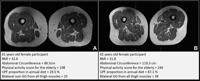

(University of California, San Francisco / Radiology via SWNS)

kAmp<<2J2[ 7C@> E96 k2 9C67lQ9EEADi^^HHH]F4D7]65F^Q E2C86ElQ03=2?<Q C6=lQ?@C676CC6C ?@@A6?6CQm&?:G6CD:EJ @7 r2=:7@C?:2[ $2? uC2?4:D4@k^2m[ 6IA=2:?65 E92E 42? 36 D66? G:2 |#x D42?D 2D 72EEJ 5686?6C2E:@? @7 E96 >FD4=6[ H96C6 DEC62<D @7 72E C6A=246 >FD4=6 7:36CD]k^Am

kAm$96 D2:5i Qx? 255:E:@? E@ :?G6DE:82E:?8 E96 BF2=:EJ @7 @FC >@56C? 5:6E :? C6=2E:@?D9:A E@ E9:89 >FD4=6 4@>A@D:E:@?[ :? E9:D DEF5J[ H6 FD65 H:56=J 2G2:=23=6[ ?@?\6?92?465 |#x[ >2<:?8 @FC 2AAC@249 2446DD:3=6 2?5 AC24E:42= 7@C C@FE:?6 4=:?:42= FD6 2?5 7FEFC6 DEF5:6D]k^Am

kAmQ%96D6 |#xD 5@ ?@E C6BF:C6 25G2?465 @C 4@DE=J E649?@=@8J[ H9:49 >62?D E96J 42? 36 62D:=J :?4@CA@C2E65 :?E@ DE2?52C5 5:28?@DE:4 AC24E:46D]Qk^Am

kAmQ%9:D :D E96 7:CDE DEF5J 2DD6DD:?8 F=EC2\AC@46DD65 7@@5VD :>A24E @? E9:89 >FD4=6 4@>A@D:E:@? FD:?8 |#x]Qk^Am